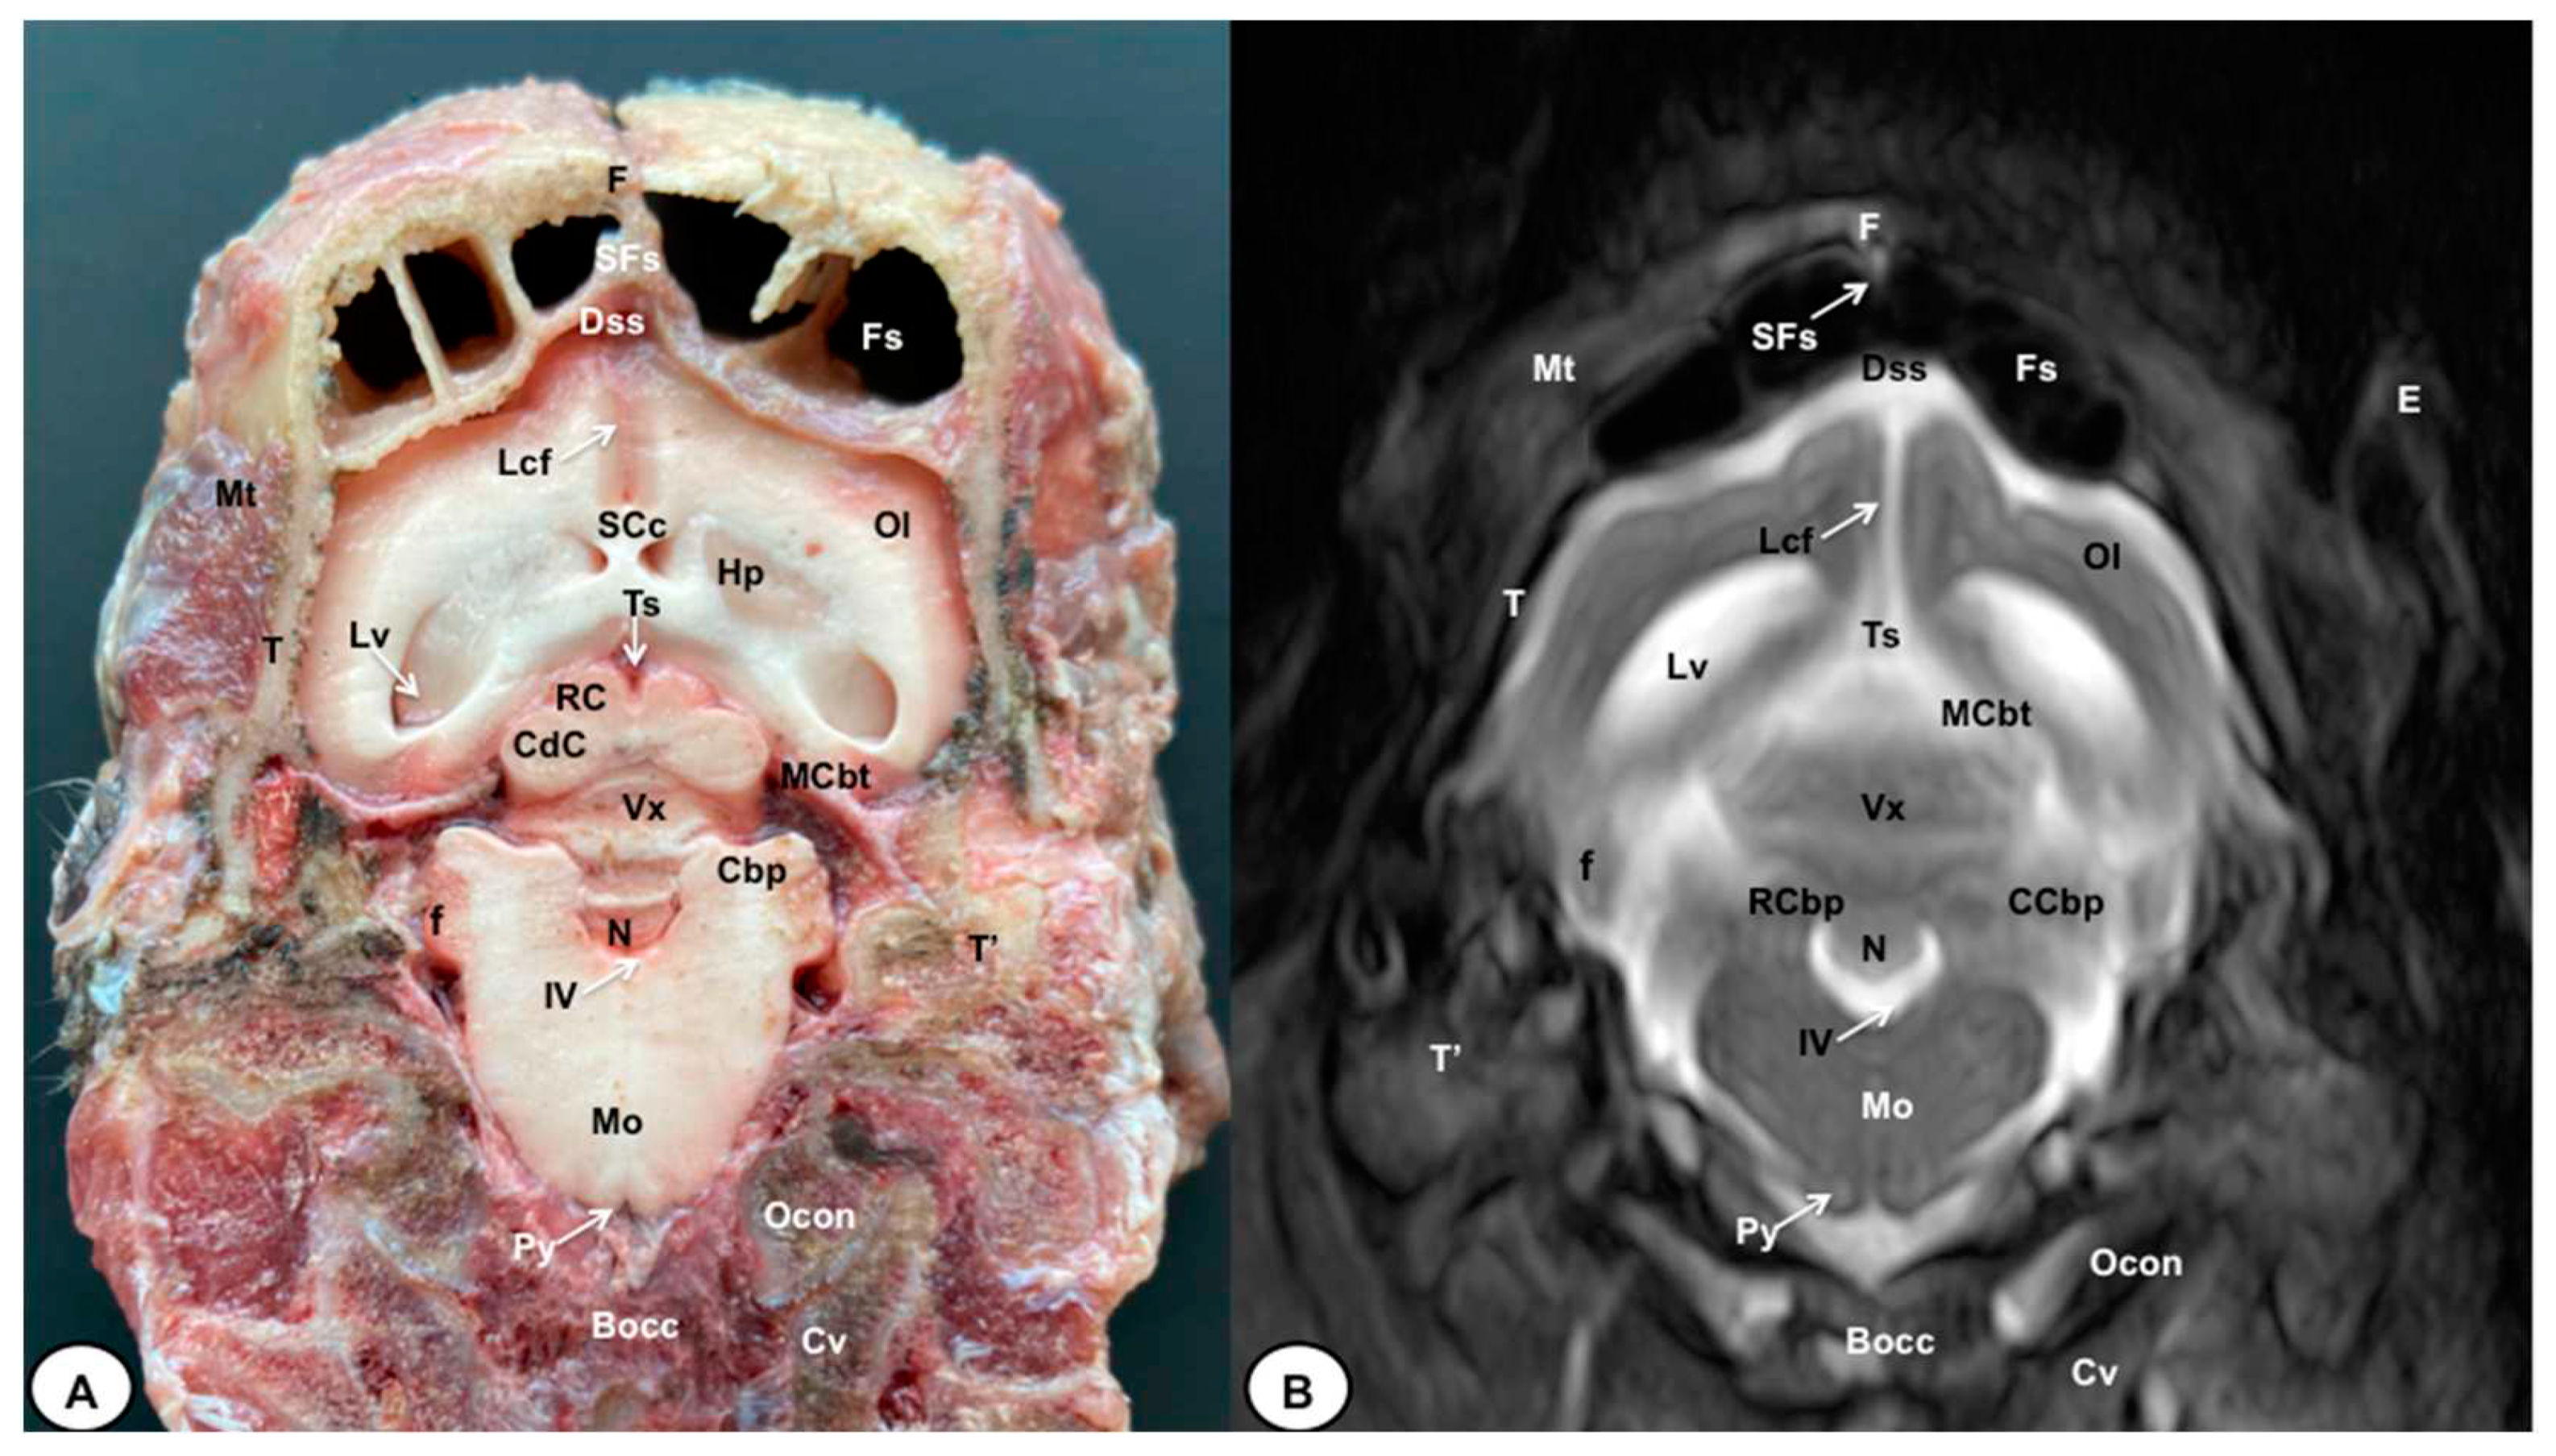

3.1. Anatomical gross-sections

3.2. Magnetic Resonance Imaging (MRI)